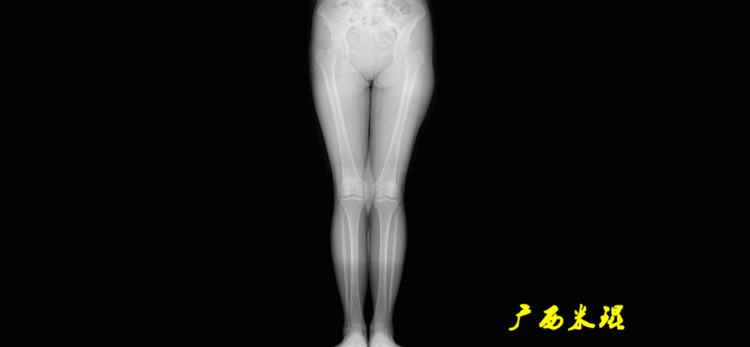

下肢力线及相关角度测量的前提是必须拍摄标准的站立位也就是负重位的下肢全长片。目前这样的照片都是放射科的技师在电脑上拼接出来的,大部分医院的DR都能够做到这一点。

患者直立于摄影架上,后背贴近摄影架,双手自然下垂,膝关节尽量伸直,足部与双肩同宽,要求投照时双髌骨朝正前方,通常患者双足尖应平行向前即可。

提醒一下大家,拍摄过程中应避免下肢的外旋和内旋。如果有一侧肢体短缩时,投照应当用脚垫垫高短缩肢体,使骨盆保持水平,这样下肢短缩测量才精确。如果有肢体旋转畸形时,还是以髌骨朝前为标准,虽然此时双足可能不能保持平行。

二、下肢全长片的基本要求

无论如何,拍摄出来的下肢全长片必须包含髋关节中心、膝关节中心及踝关节中心,否则对临床是无用的。有了一张下肢的全长照片,我们需要确定下肢关节的中心点,通过中心点画出下肢的各种轴线,然后利用轴线与关节线的相交得出各种所需要的角度。